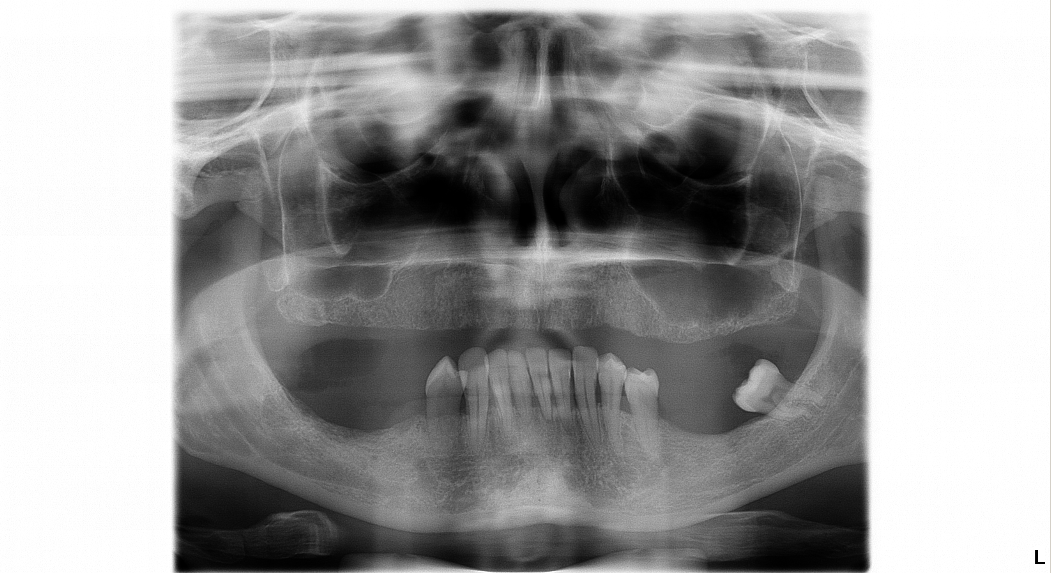

Poprípade by nám pomohlo, ak by ste nám poslali aspoň Vašu OPG rontgenovú snímku emailom, aby sme mali predstavu o stave Vášho chrupu a vedeli Vám povedať bližšie informácie o cene.

Vedeli by ste nám poslať RTG snímku, alebo fotografiu Vašich zubov? Záleží od toho koľko zuby sme museli trhať, koľko implantátov by bolo potrebných a pod.